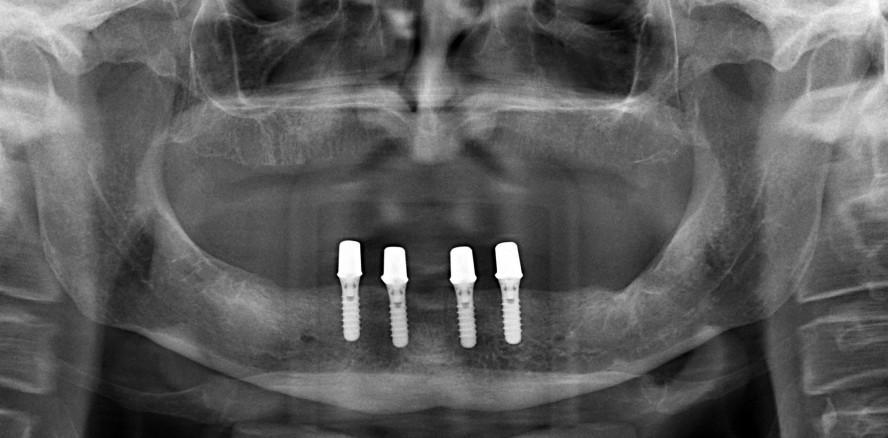

Foto: © Prof. Dr. Matthias Karl

Grundsätzlich ist zwischen individuell gefertigten Attachments wie Stegen (Abb. 1) und Teleskopen (Abb. 2) sowie präfabrizierten Elementen wie Magneten, Kugelkopfankern und Locatoren sowie Locator-ähnlichen Attachments (Abb. 3) zu unterscheiden. Die Verblockung der Implantate wird unter Hygieneaspekten kritisch gesehen. Die individuelle Fertigung ist dabei zweifelsohne kostenintensiver als die Nutzung von Standard-Attachments, in deren Gruppe sich vor allem die Locatoren durchgesetzt haben.

Zur Abschätzung der klinischen Relevanz der genannten Überlegungen wurden die Behandlungsdaten von 29 unbezahnten Patienten der Klinik für Zahnärztliche Prothetik und Werkstoffkunde des Uniklinikums des Saarlandes (UKS), die mit insgesamt 100 Implantaten und Locatoren oder Locator-ähnlichen Attachments abnehmbar versorgt wurden, retrospektiv ausgewertet. In den ersten drei Monaten nach Eingliederung der Prothesen kam es bei den Patienten zu 16 Attachment-bedingten Komplikationen und innerhalb der ersten zwei Jahre zu weiteren 15 Komplikationen. Zudem wurden in der Kohorte weitere 25 Komplikationen mit Bezug zum Verankerungselement registriert. Der mit Abstand häufigste Grund für eine Wiedervorstellung der Patienten war ein Retentionsverlust des Attachments, gefolgt von der Lockerung bzw. dem Verlust der Attachment-Patrize. Die maximale Zahl an Nachbesserungen bei einem Patienten betrug zehn Interventionen. Bei vergleichbaren Kohorten, die mittels Teleskopen bzw. Stegen restauriert worden waren, kam es zu statistisch signifikant weniger Komplikationen. Um die Relevanz der Ergebnisse weiter bestätigen zu können, besteht allerdings zukünftiger Forschungsbedarf.